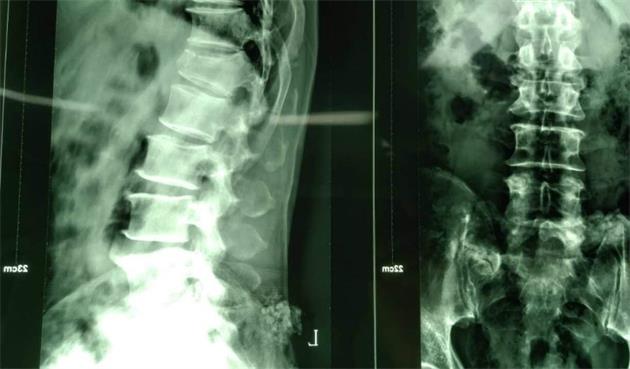

該系統是針對胸腰椎后路微創(chuàng )手術(shù)設計的經(jīng)皮內固定系統,采用“自通道”設計,置釘時(shí)無(wú)需釘尾延長(cháng)裝置,簡(jiǎn)化了微創(chuàng )手術(shù)經(jīng)皮固定的操作步驟,顯著(zhù)地縮短了手術(shù)時(shí)間。同時(shí),超長(cháng)的釘尾設計,超重患者不再是顧慮,適用范圍更廣!